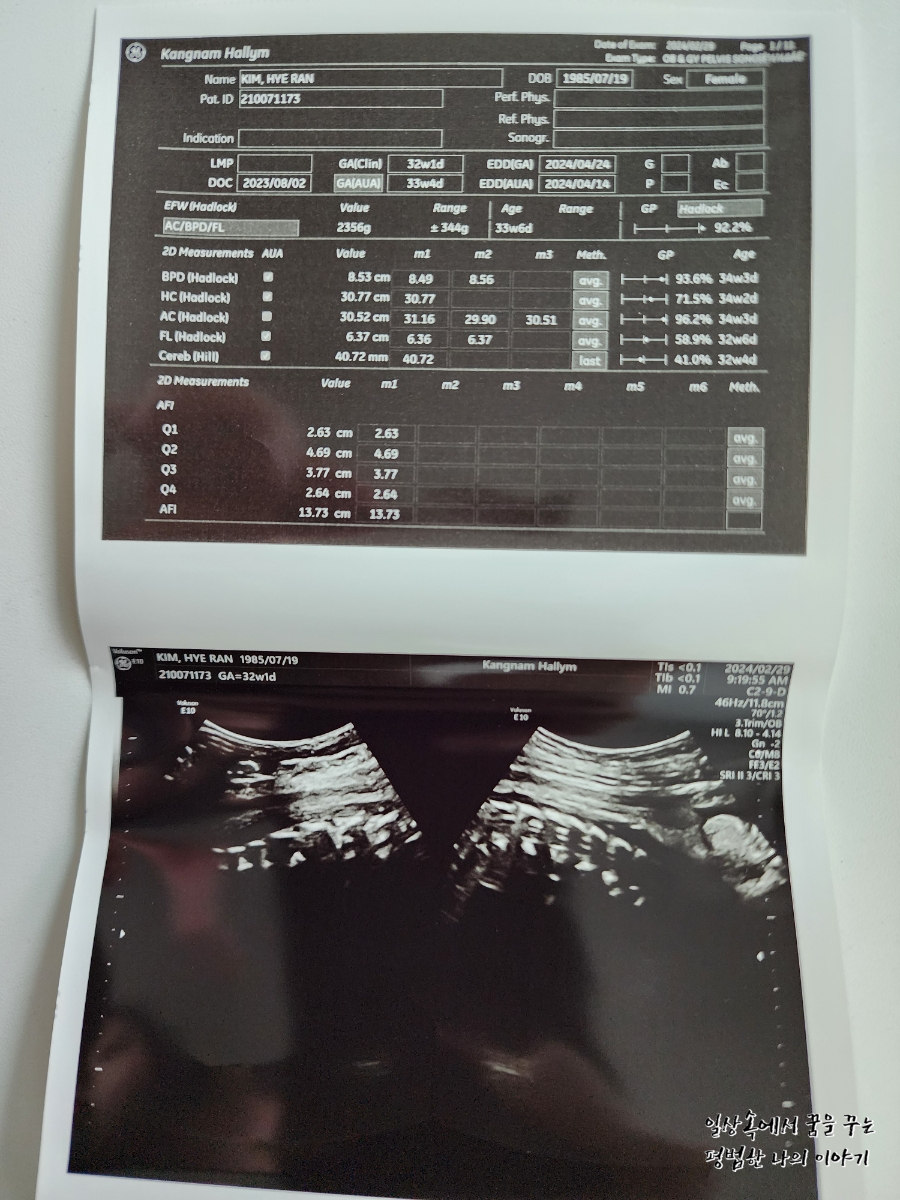

BPD(Biparietal Diameter, 위에서 볼 때 태아 머리 단면의 가장 긴 길이): 8.53cm

HC(Head Circumference, 태아 머리둘레): 30.77cm

AC(Abdominal Circumference, 배 둘레): 30.52cm

EDD(Expected Date of Delivery, 출산 예정일): 2024년 4월 24일

FL(Femur Length, 허벅지뼈 길이): 6.37cm

GA(Gestational Age, 임신 주차): 32주 차 1일

EFW(Estimated Fatal Weight, 태아 예상 체중)=EBW(Estimated Body Weight): 2356g

AF(Amniotic Fluid, 양수): 정상